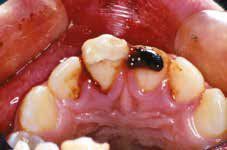

Enamel-dentine fracture is a complete fracture of the tooth enamel and dentine without the exposure of the pulp. Pulp sensibility testing is recommended to confirm pulpal health. Treatment depends on how close the fracture is in relation to the pulp. If a tooth fragment is available, it can be bonded to the tooth.